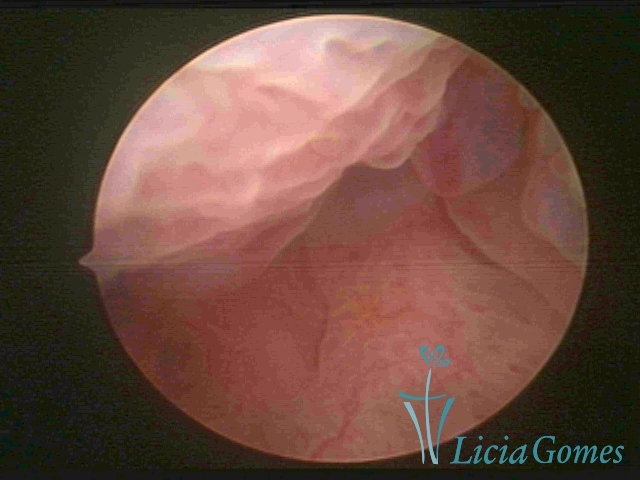

First part or proximal section or lower section:

During the proliferative phase, a light, crystalline mucus with a low adherence to the scope is found. The crypts and buds are a little swelled and vascularized, microvesicular, resembling grape clusters.